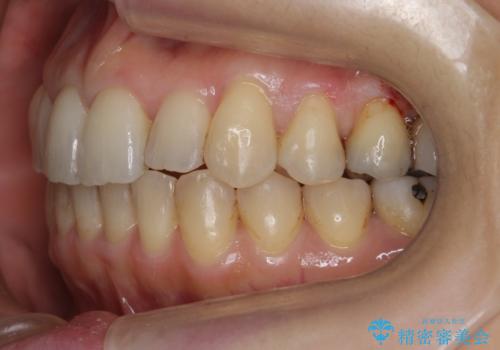

- 前歯のガタガタを主訴に来院。

前歯は開咬傾向であり、小臼歯から大臼歯にかけてもオーバージェットは非常に小さく咬耗していました。

非抜歯で前歯の重なりを作るのは難しいとご説明しましたが、インビザラインでできるところまで並べていくことになりました。

途中再評価を行い、矯正用のミニスクリューを用いて奥歯を遠心移動し、前歯の出っ歯傾向を改善しました。

左上12の段差についてはここまで直すのにもかなり時間がかかりました。インビザライン単独では限界があると説明し、ワイヤーの部分矯正もご提案しましたが、患者様のご希望によりインビザラインでできるところまで頑張るということで4回ほどリファインメントを行いました。